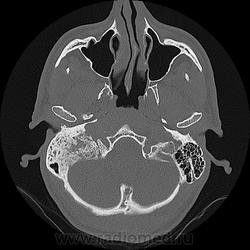

Не знаю в чем КТ может противоречить МРТ, но на КТ имеется нарушение  структуры костей основания черепа справа (мыщелка затылочной кости, затылочной и височной костей). Заинтересована и стенка внутреннего слухового прохода. О характере процесса с уверенностью высказаться не могу, но отит (на мой взгляд) тут не причем (барабанная полость и антрум свободны). Имеется содержимое и неровность стенок ячеек правого сосцевидного отростка. Может мастоидит, какой-нибудь небанальный, с петрозитом? Хотя, как это может поразить еще и затылочную кость?

В МРТ не разбираюсь. Думаю, ошибочно могло быть интерпретировано по КТ как фиброзная дисплазия. Нашла , на мой взгляд, подходящие варианты: http://translate.google.ru/translate?hl=ru&langpair=en%7Cru&u=http://www.ncbi.nlm.nih.gov/pmc/articles/PMC2702196/

Особенно похожа иллюстрация по КТ:

Даже если так описано, то не ошибочно. Имеет право быть. Но с Вами согласен - больше за гемангиому.